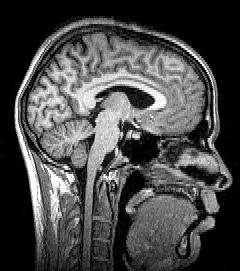

التصوير العصبي Neuroimaging، يتضمن استخدام تقنيات مختلفة للتصوير المباشر أو الغير مباشر للبنية، الوظيفة/علم عقاقير المخ. وهو فرع جديد نسبيا في الطب وعلم الأعصاب/علم النفس.[1]

- تصوير بنيوي، والذي يتعامل مع بنية المخ وتشخيص إجمالي (واسع النطاق) للأمراض القحفية (مثل الأورام)، الجروح.

التصوير بالرنين المغناطيسي